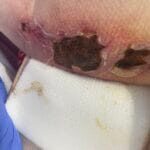

Enrolled Nurse (EN): Permitted Procedures

This page provides a quick reference of Care Plans and Tutorials available on The Wound Sandwich (TWS) which are permitted to be undertaken by staff with a Enrolled Nurse (EN) qualification. Additional applicable qualifications are also listed.